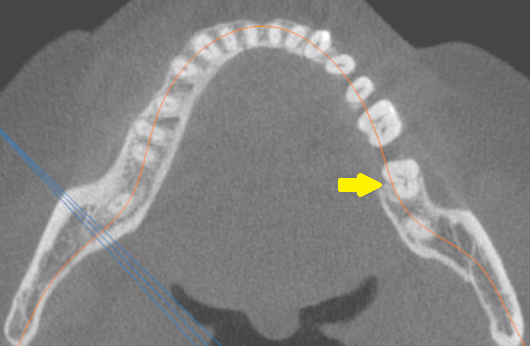

Ryc. 1. Badanie CBCT żuchwy – przekrój poprzeczny. Strzałką zaznaczono drugi ząb trzonowy żuchwy z kanałem typu C.